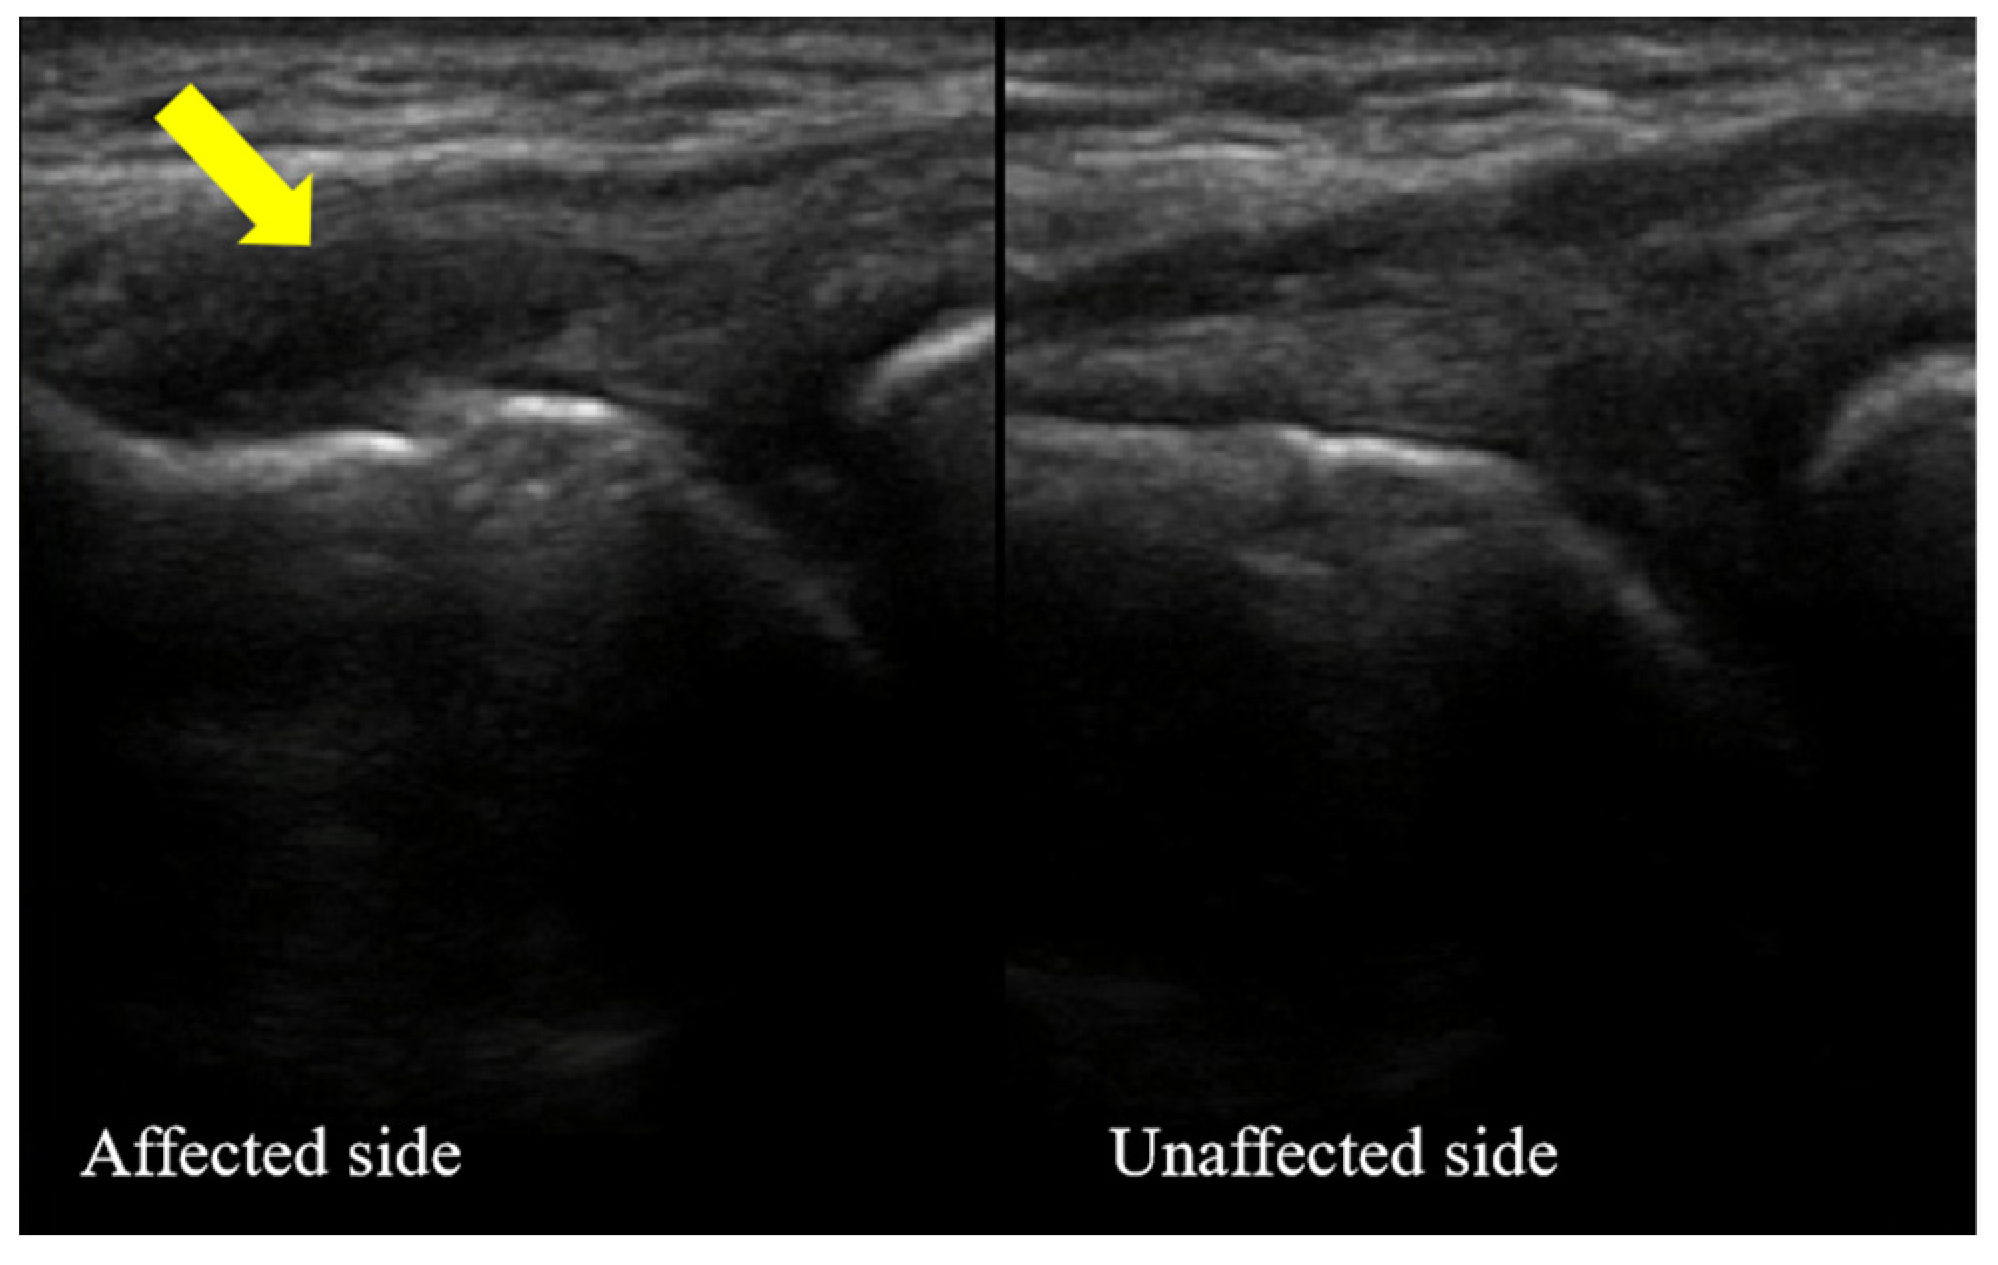

Characteristic of Ultrasonography

3.2. Ultrasonography Evaluation

3.2.1. Case One

3.2.2. Case Two